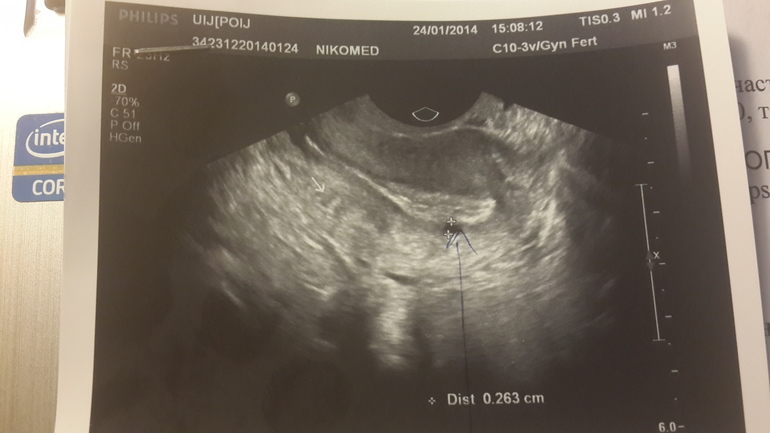

Гинекологические заболеванияДевчата, кому ставили такой диагноз по узи... откликнитесь! Мне очень нужны фото ваши с узи с маткой! Сегодня на 23 дц увидели эхрнегативное включение 3мм, по передней стенке матки! Никогда я подобного не видела! Всегда все было хорошо! В начале цикла такого не наблюдали! Прошу покидайте фото кому не сложно! Буду очень благодарна вам! И как лечились и беременели! фото под катом

Оба фото с сегодняшнего узи! На первом толком ничего не видно! только хороший эндик.

А вот на втором, датчик иначе доктор повернула, видно образование!